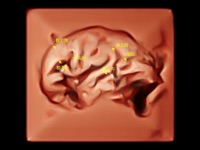

作為開立醫(yī)療全新打造的超高端旗艦超聲產(chǎn)品,從探頭抬起喚醒開啟掃查到多維探頭發(fā)射接收,通過先進(jìn)的場(chǎng)成像發(fā)射、自適應(yīng)聚合重建等技術(shù),基于RF Data原始射頻數(shù)據(jù)在圖像生成、高端功能等方面實(shí)現(xiàn)突破,為婦產(chǎn)科、兒科提供全方位臨床解決方案。